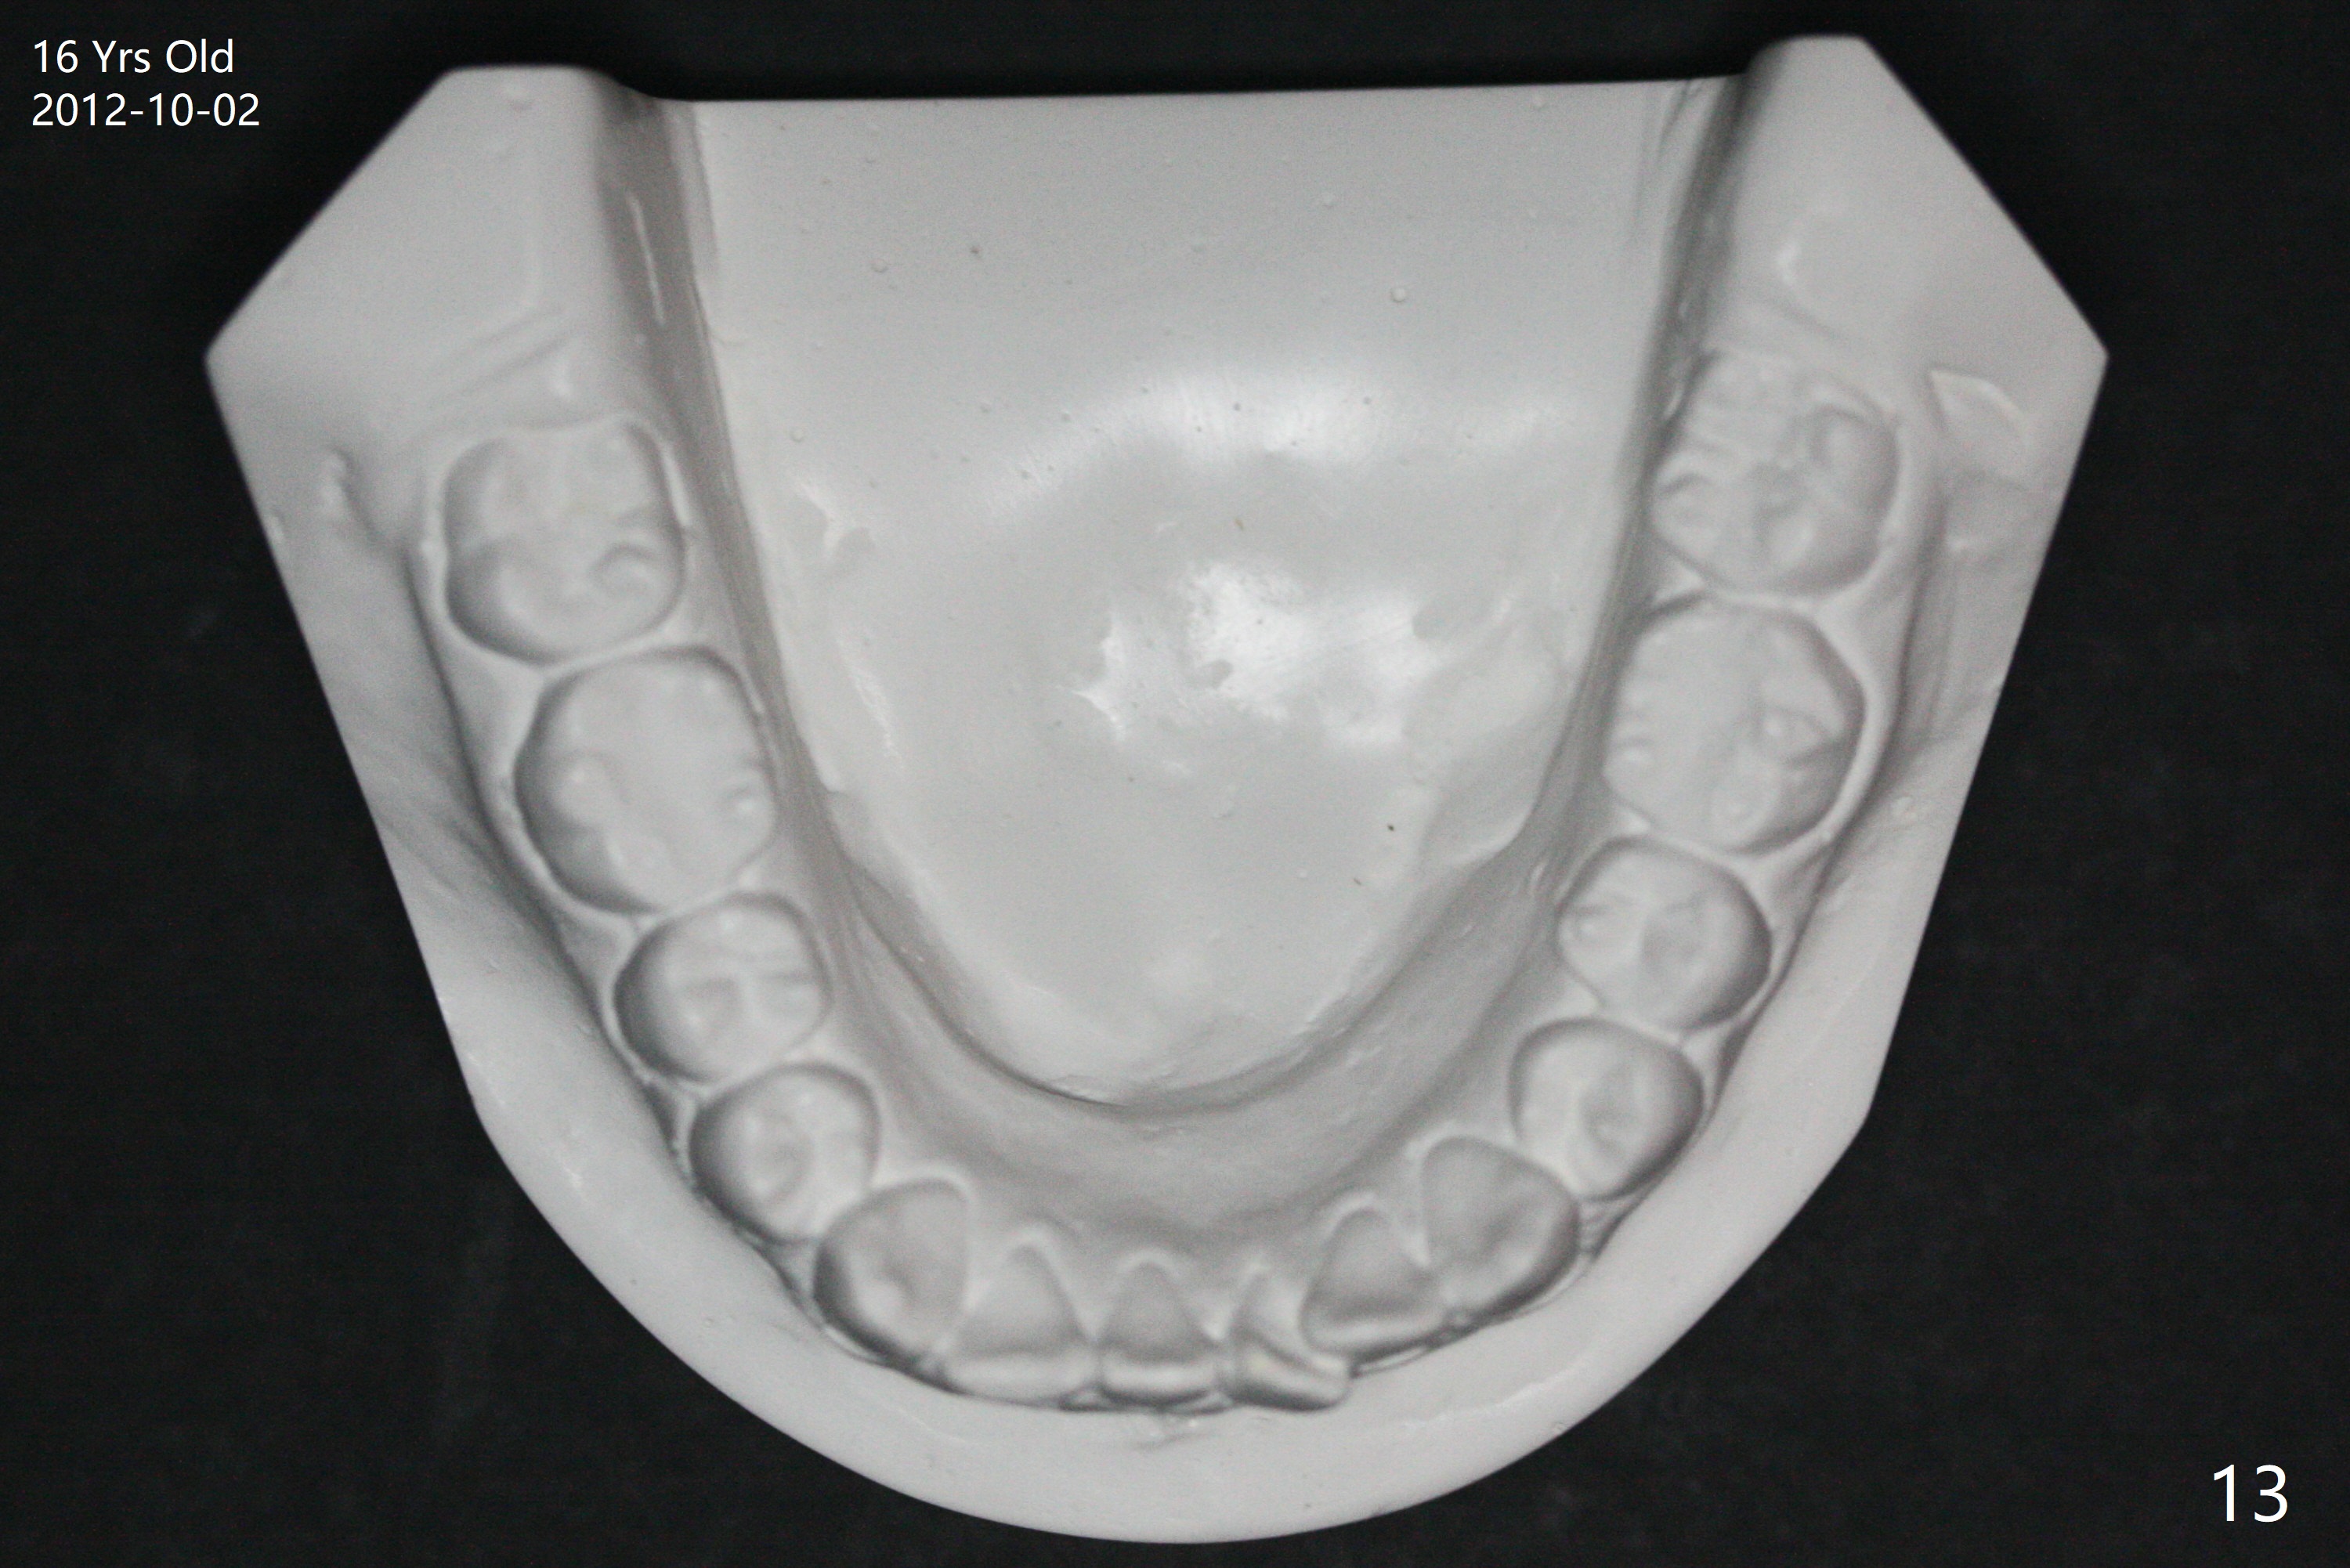

A 16-year-old man has severe crowding, but the open bite is ignored (Fig.1,4,7,10,13). The orthodontic treatment lasts 4 years 5 months, including failure to return for a period of time. The open bite seems to have been corrected (Fig.2, 5, 8, 11, 14). Suction down retainers are provided. In less than 2 years, the patient returns requesting remaking retainers. It appears that open bite relapses (Fig.3,6,9,12,15), as related to supraeruption of the lower 2nd molars (Fig.6,9 arrows). The latter is apparently associated with the erupting 3rd molars.